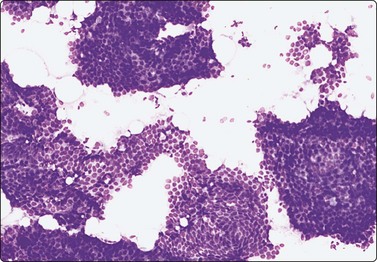

image image

Fig. 7.20 Fibroadenoma

Cell-rich smear of elongated, branching fragments of ductal epithelium and numerous single bipolar nuclei in the background (A, MGG; B, Pap; LP).

Criteria for diagnosis

Cellular smears with a bimodal pattern containing epithelial and stromal fragments,

Large, branching sheets of bland epithelial cells,

Numerous single, bare bipolar/oval nuclei,

Fragments of fibromyxoid stroma.

Fibroadenoma is one of the most common benign mammary neoplasms sampled by FNB. Aspiration biopsy is a highly reliable diagnostic procedure in the diagnosis of fibroadenoma when combined with clinical and imaging findings with a sensitivity reaching 97% and specificity, positive predictive value and negative predictive value reported to be 94%, 79% and 98%, respectively.109,110 Fibroadenomas are usually well-circumscribed lesions and have a characteristic rubbery consistency felt through the needle. Smears show a bimodal pattern of non-neoplastic breast tissue but are more cellular (Fig. 7.20). The epithelial fragments of regularly arranged, cohesive cells are large, elongated and branching, stag-horn-like, reflecting the appearance in tissue sections. There is variable nuclear crowding and overlapping. The nuclei are often mildly enlarged but uniform, have a bland granular chromatin pattern and often one or two small, indistinct nucleoli. Single, bare bipolar/oval nuclei are scattered in the background. They are characteristically numerous, much more numerous than in the usual glandular breast tissue, except in fibrotic and sclerosed fibroadenomas. Myoepithelial cell nuclei are also frequently seen within the epithelial aggregates. Sometimes, epithelial cells with apocrine differentiation may be prominent, and large numbers of foamy macrophages may suggest a cystic component. Fragments of fibromyxoid stroma are obtained from most but not all fibroadenomas. They stain pink to magenta with MGG, pale bluish-green with Pap, have a fibrillary structure and contain spindled fibroblastic nuclei (Figs 7.21-7.23). There may be a film of myxoid ground substance in the background. Smears from fibroadenoma with abundant collagenous stroma and scanty epithelium are less characteristic and may not differ much from the usual non-neoplastic breast tissue or fibrocystic change.